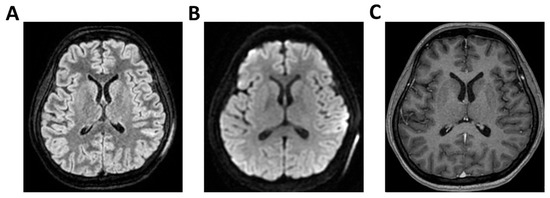

Figure 3.

MRI of patient 3 group 1. A 49-year-old man with pneumococcal meningitis was transferred to INMI L. Spallanzani after 10 days of right-sided otalgia, fever, and headache. On arrival, he was alert and oriented but exhibited psychomotor slowing. Physical exam revealed positive Kernig’s, Brudzinski’s, and Lasegue’s signs. Brain CT was negative for acute lesions but showed bilateral maxillary sinusitis and right-sided otomastoiditis. Lumbar puncture revealed cloudy CSF with 4069 cells/mm3, low glucose (36 mg/dL), and elevated protein (180 mg/dL). FilmArray was positive for Streptococcus pneumoniae; urinary antigens for Legionella pneumophila and S. pneumoniae were negative. The patient was started on Vancomycin, Ceftriaxone, and Dexamethasone. The next day, he became mute and poorly cooperative, prompting transfer to the ICU. TCCD showed normal PI (1.18 right, 1.02 left) with no signs of intracranial hypertension. (A) 3D axial T1 FSPGR (Fast Spoiled Gradient Recalled) shows mild and diffuse increase in physiological pachymeningeal enhancement, with no specific significance. Morphology and signal intensity of brain tissue is normal. (B) 3D axial FLAIR confirms right-sided otomastoiditis and (C) bilateral maxillary sinusitis.

3.1. Group 1: TCCD and Standard MRI (FLAIR and DWI)

Regarding etiology, two cases, case 1 and 5 (40%), were due to pneumococcal meningitis, while the remaining were neurotoxoplasmosis (n = 1, 20%) (case 2), Varicella-Zoster virus meningoencephalitis (n = 1, 20%) (case 3), and meningoencephalitis of undetermined origin (n = 1, 20%) (case 4). Three out of five patients demonstrated normal or mildly elevated pulsatility indices (PI ≤ 1.18) and no waveform signs of intracranial hypertension. In these cases, MRI findings were either normal or showed non-specific alterations, such as mild pachymeningeal enhancement or limited subcortical lesions, without mass effect or restricted diffusion. All three patients in this subgroup experienced full neurological recovery at 28 days (GOS 5) (Table 2 and Figure 1, Figure 2 and Figure 3).